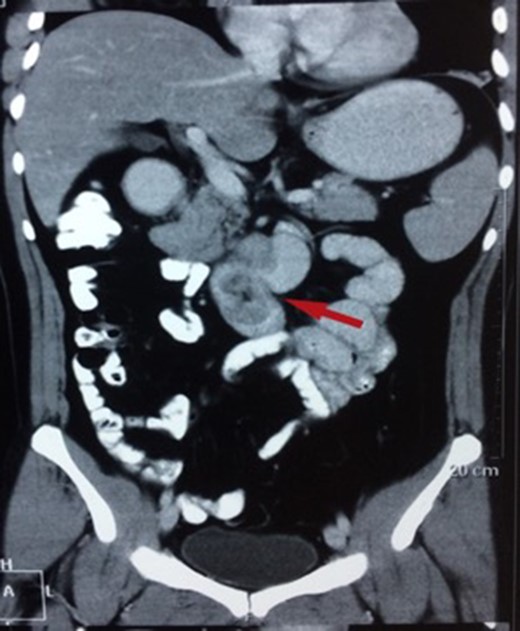

There were three males and one female who had Brunner’s gland hyperplasia as the pathological finding in their surgical specimens following operations for duodenal lesions. Their mean age at presentation was 39.7 ± 10.14 (range: 30–52) years and their presenting features were abdominal pain in two patients, vomiting (2), and upper gastrointestinal bleeding (2). The duration of their symptoms varied between 4 days and 4 years prior to presentation. All patients underwent an upper gastrointestinal endoscopy (Figs 1 and 2) and abdominal computed tomography(Figs 3 and 4) scans as part of their evaluation. The details of patient presentation, evaluation, surgical procedure and outcomes are described in Table 1.

CT showing a polypoid lesion extending from the first part of the duodenum and projecting into the lumen of the second and third part.

| Case 2 | 44/M | 4 days | Malena, fatigue requiring blood transfusions | 60 × 45 mm2 mildly enhancing solid mass involving second and third part of duodenum with exophytic contour bulge likely polypoid lesion (Fig. 4) | A Large friable polypoidal lesion at junction of second and third part of duodenum | Non-specific chronic duodenitis with focal mild dysplasia | Transduodenal polyp excision (Fig. 5) | 2 | 1 | 5 |

These lesions are often difficult to differentiate from other submucosal lesions in this location pre-operatively from gastrointestinal stromal and neuroendocrine tumours. Large adenomas can be detected by ultrasonography and computed tomography [8]. CT is also useful to confirm the absence of extra-luminal extension of a Brunner’s gland adenoma [9]. In our series, all patients were symptomatic at presentation and were being evaluated for these, and lesions found incidentally (e.g. after pancreaticoduodenectomy specimens for cancer) were excluded.